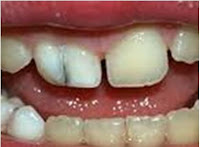

Anomali gigi yaitu gigi yang bentuknya menyimpang dari bentuk aslinya. Geminasi dan fusi atau yang dikenal sebagai gigi kembar merupakan salah satu bentuk  anomali atau kelainan pada gigi. Geminasi adalah suatu keadaan satu benih gigi yang mengalami proses pemisahan tidak sempurna pada saat perkembangannya, sehingga mahkotanya tampak terbelah menjadi dua tetapi memiliki satu akar.

Geminasi  lebih sering terjadi pada gigi seri sulung rahang bawah dan gigi seri permanen rahang atas. Secara klinis terlihat sebagai mahkota yang terbelah menjadi dua. Laki-laki dan perempuan sama-sama dapat mengalami geminasi. Perawatan geminasi dapat dilakukan dengan mengeluarkan struktur/daerah gigi yang mengalami geminasi kemudian mahkotanya diperbaiki dan dibentuk ulang. Selain itu juga dapat dengan mengurangi lebar mesio-distal gigi atau preparasi jaket dan dibungkus dengan mahkota jaket.

Secara klinis, geminasi dan fusi terlihat sama dan mungkin sulit untuk dibedakan serta harus dilihat pada hasil foto rontgen untuk membedakannya secara pasti. Tetapi untuk menentukan diagnosis sementaranya apakah itu geminasi atau fusi, dapat dilakukan dengan menghitung jumlah gigi. Misalnya pada gigi anak-anak rahang bawah jumlahnya 10 gigi. Pada kasus geminasi, karena 1 gigi terbelah menjadi 2, maka jika kita menghitung jumlah giginya, akan terdapat kelebihan 1 gigi  menjadi 11, sedangkan pada fusi (dua gigi berdempet menjadi satu) tidak ditemukan kelebihan gigi.